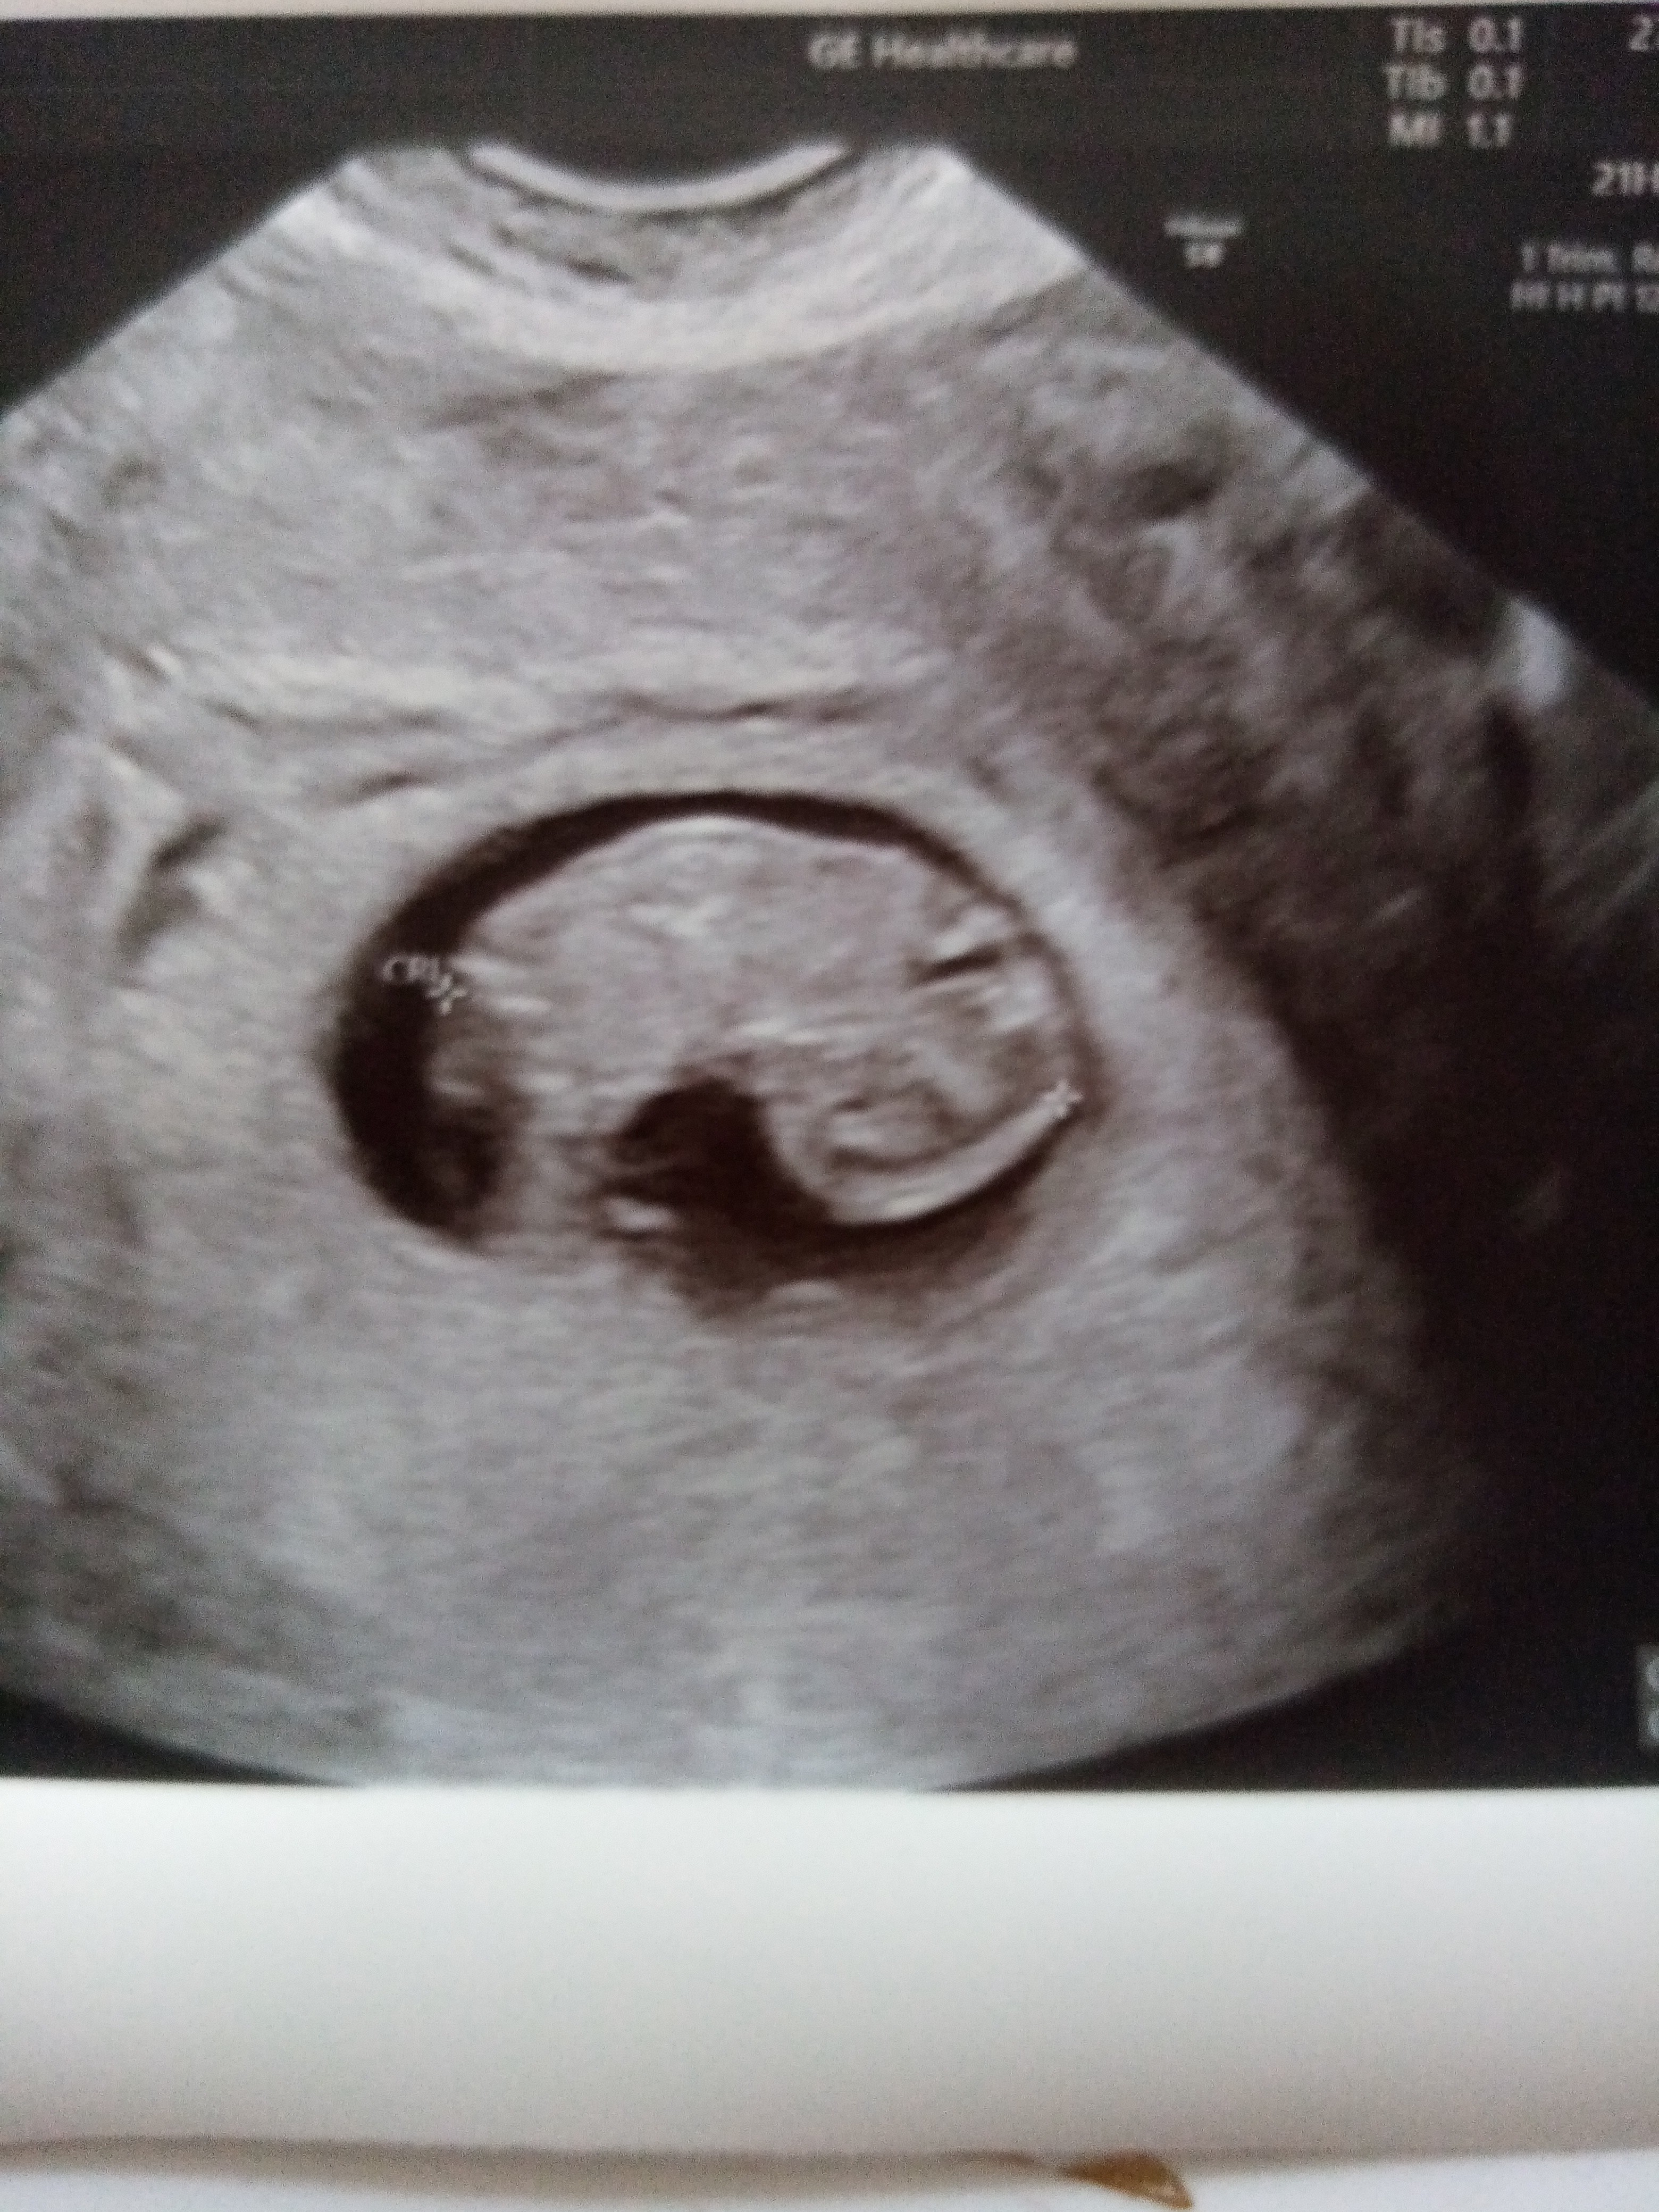

Ja niestety w szpitalu i właśnie jutro chcą mi robić usg. Niestety, wieczorem krwawienie było chwilowo tylko podczas podcierania, ale rano znów ze mnie chlusnelo jak poszłam do ubikacji. Staram się jakoś o tym nie myśleć, choć przykro mi, że się znowu nie udało

może zarodek chory, nie mam pojęcia... na razie skurczy nie mam, tylko ciągle krwawienie, rano normalnie jak miesiaczka, momentami mniejsze. Daja mi tu jedynie duphaston ale nie sądzę żeby krwawienie było przez prog - sprawdzałam kilka dni temu i był na poziomie 43, a wcześniej żadnego duphastonu ani luteiny nie brałam.